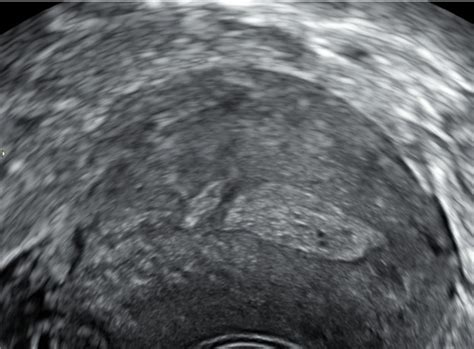

- Transvaginalni ultrazvok: Omogoča vizualizacijo notranjosti maternice in odkrivanje polipov.

- Sonohisterografija (ultrazvok s fiziološko raztopino): V maternično votlino se vbrizga sterilna fiziološka raztopina, ki razširi votlino in omogoči boljšo vizualizacijo polipov z ultrazvokom.